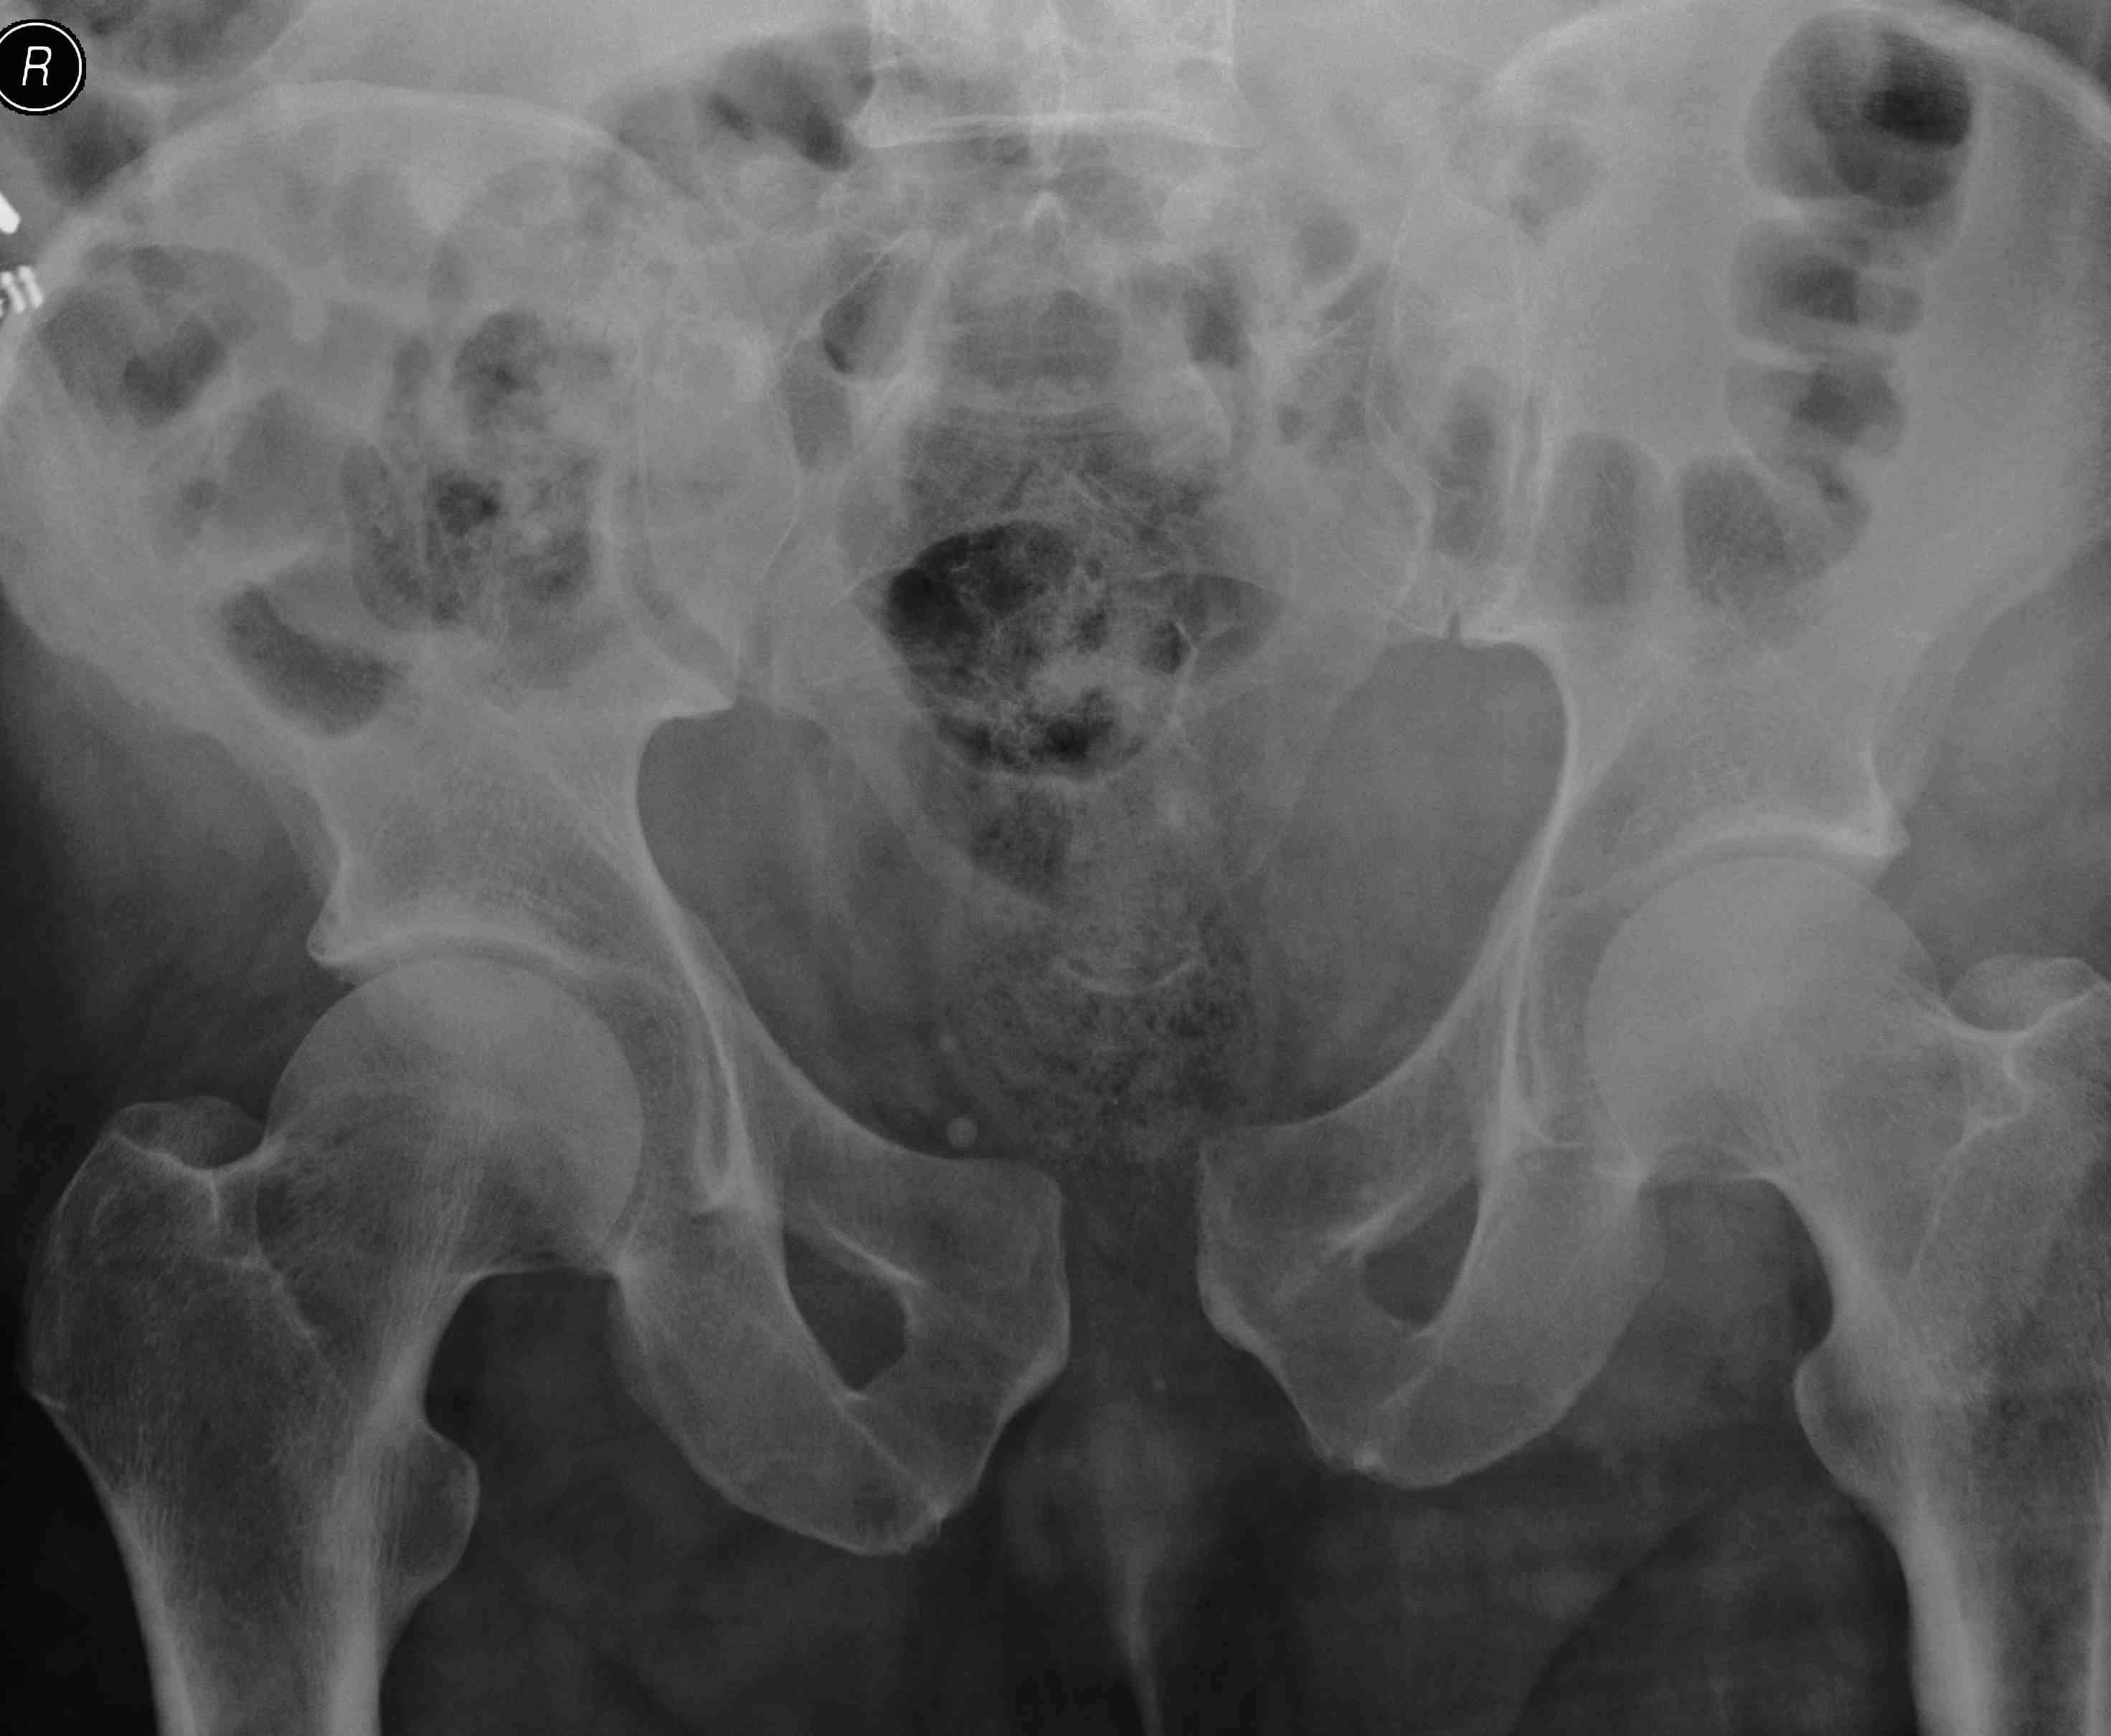

APC-3

APC 3Complete SI joint disruption

Pubic diastasis > 5 cm with complete SI joint disruption